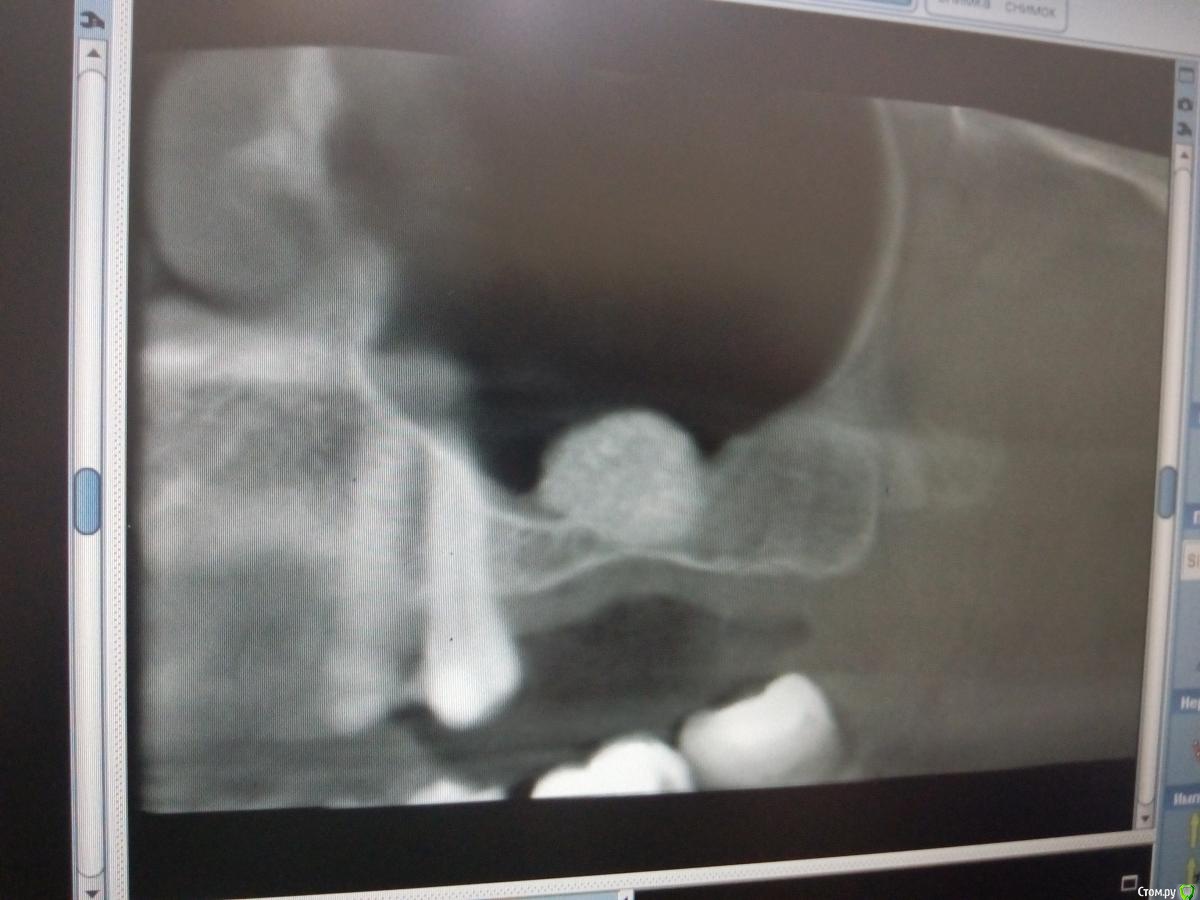

Sampson Опубликовано 14 августа, 2018 Поделиться Опубликовано 14 августа, 2018 (изменено) В феврале провел первый свой открытый синус.Снимок доПосле операцииНеделю назад пришла на контроль. Изменено 14 августа, 2018 пользователем Sampson Ссылка на комментарий

колесников Опубликовано 14 августа, 2018 Поделиться Опубликовано 14 августа, 2018 (изменено) То что вы отслоились небной-это превосходно! Обычно,по началу,многие побаиваются углубляться и дальше окна не ходят. Но я бы рекомендовал ещё мезиодистально отслаиваться. Теперь спереди и сзади от графита ямы для скапливания слизи ,причина пролиферации шнейдеровой. Изменено 14 августа, 2018 пользователем колесников 2 Ссылка на комментарий

Bier Опубликовано 14 августа, 2018 Поделиться Опубликовано 14 августа, 2018 согласен с Колесниковым, медиально надо было шире значительно. Теперь даже позиция имплантата не очень то выходит.. В натяг попадаете в медиальный край аугментата. Ссылка на комментарий

pit Опубликовано 14 августа, 2018 Поделиться Опубликовано 14 августа, 2018 Из этого случая надо просто сделать вывод и впредь делать доступ медиальнее и протяженнее. Или 2 окна. В данном случае я бы установил имплантаты в центр аугментата и в позицию "полвосьмого" зуба и сделал бы 3 коронки. 26 зуб - консольная единица, отмоделировал как премоляр. Лучшее объяснение больному, на вопрос: "почему 3 коронки?" - в необходимой позиции не выросла костная ткань, поэтому имплант ставится дальше от 25 зуба и если делать 2 коронки, как запланировано, то постоянно будет забиваться пища и это будет невыносимо противно) 1 Ссылка на комментарий